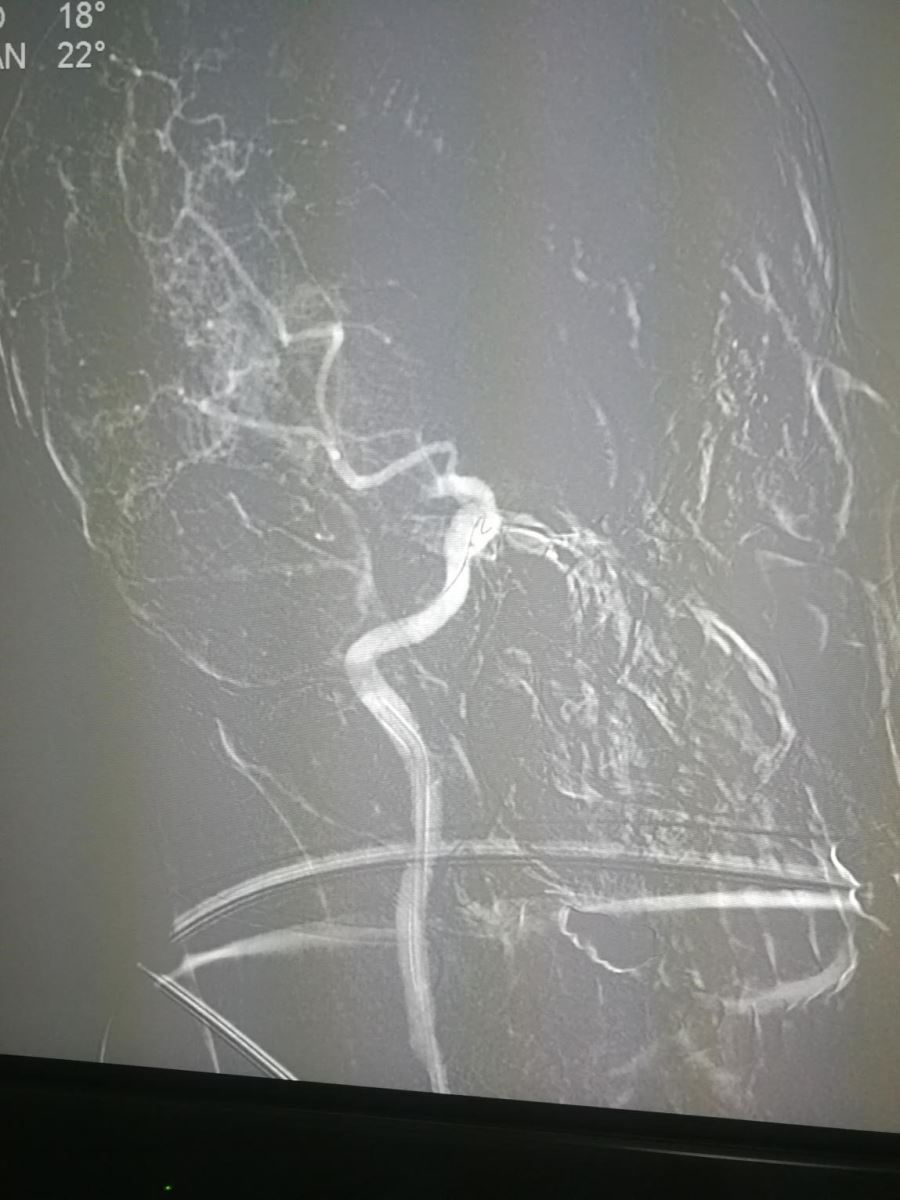

因患者到我院在发病时间窗内(<4.5h),与患者家属谈话征得其同意后,急诊立即给予阿替普酶(rt-PA)静脉溶栓,同时直接将患者送入导管室,桥接行全脑血管造影术(DSA),提示右侧颈总动脉末端闭塞(图1、2)。因患者半年前于我科行全脑血管造影术提示右侧颈内动脉未见异常(图3),此次突然发病,考虑心源性栓塞。此类栓子溶栓效果差,造影也提示溶栓无效果,积极给予支架取栓治疗。

应用抽吸方法以及支架Solitaire(6mm×20mm)取栓,可见大部分血栓取出(图4、图5),

但小部分血栓向远端移动,堵塞右侧大脑中动脉(图6),如右侧大脑中动脉不能开通,患者预后仍会较差。

于是再次用支架取栓,右侧大脑中动脉再通(图7)。

术后再次造影,可见右侧颈总动脉完全通畅(图8、图9)。